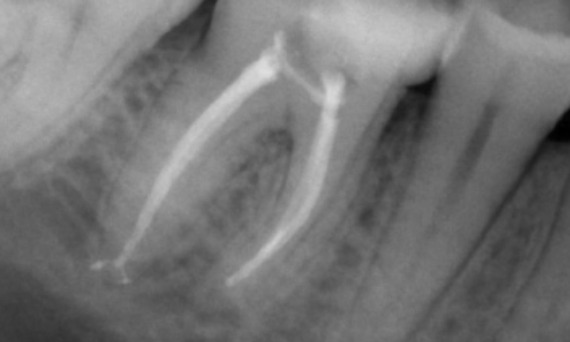

Before: Periapical radiolucency associated primarily with the distal root and loss of lamina dura on the mesial root.

After: TruNatomy was chosen in this case to allow a caries leveraged approach and a focus on pericervical dentin preservation especially on the mesial aspect where the tooth had a more minimal restoration.